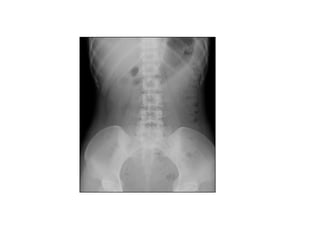

KUB BÌNH THÖÔØNG

 Thaáy ñöôïc caùc cô quan sau:

o Gan: thaáy ñöôïc bôø sau bôûi lôùp môõ sau phuùc maïc

o Laùch: coù theå thaáy ñöôïc

o Thaän: coù theå thaáy khoâng hoaøn toaøn

o Cô Psoas: bôø thöôøng thaáy roõ

o Daûi môõ caän phuùc maïc

 Nhöõng caáu truùc naøy khoâng phaûi luoân thaáy roõ